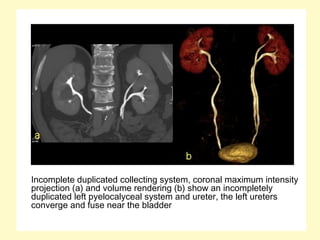

Incomplete duplicated collecting system, coronal maximum intensity

projection (a) and volume rendering (b) show an incompletely

duplicated left pyelocalyceal system and ureter, the left ureters

converge and fuse near the bladder

Incomplete duplicated collecting system